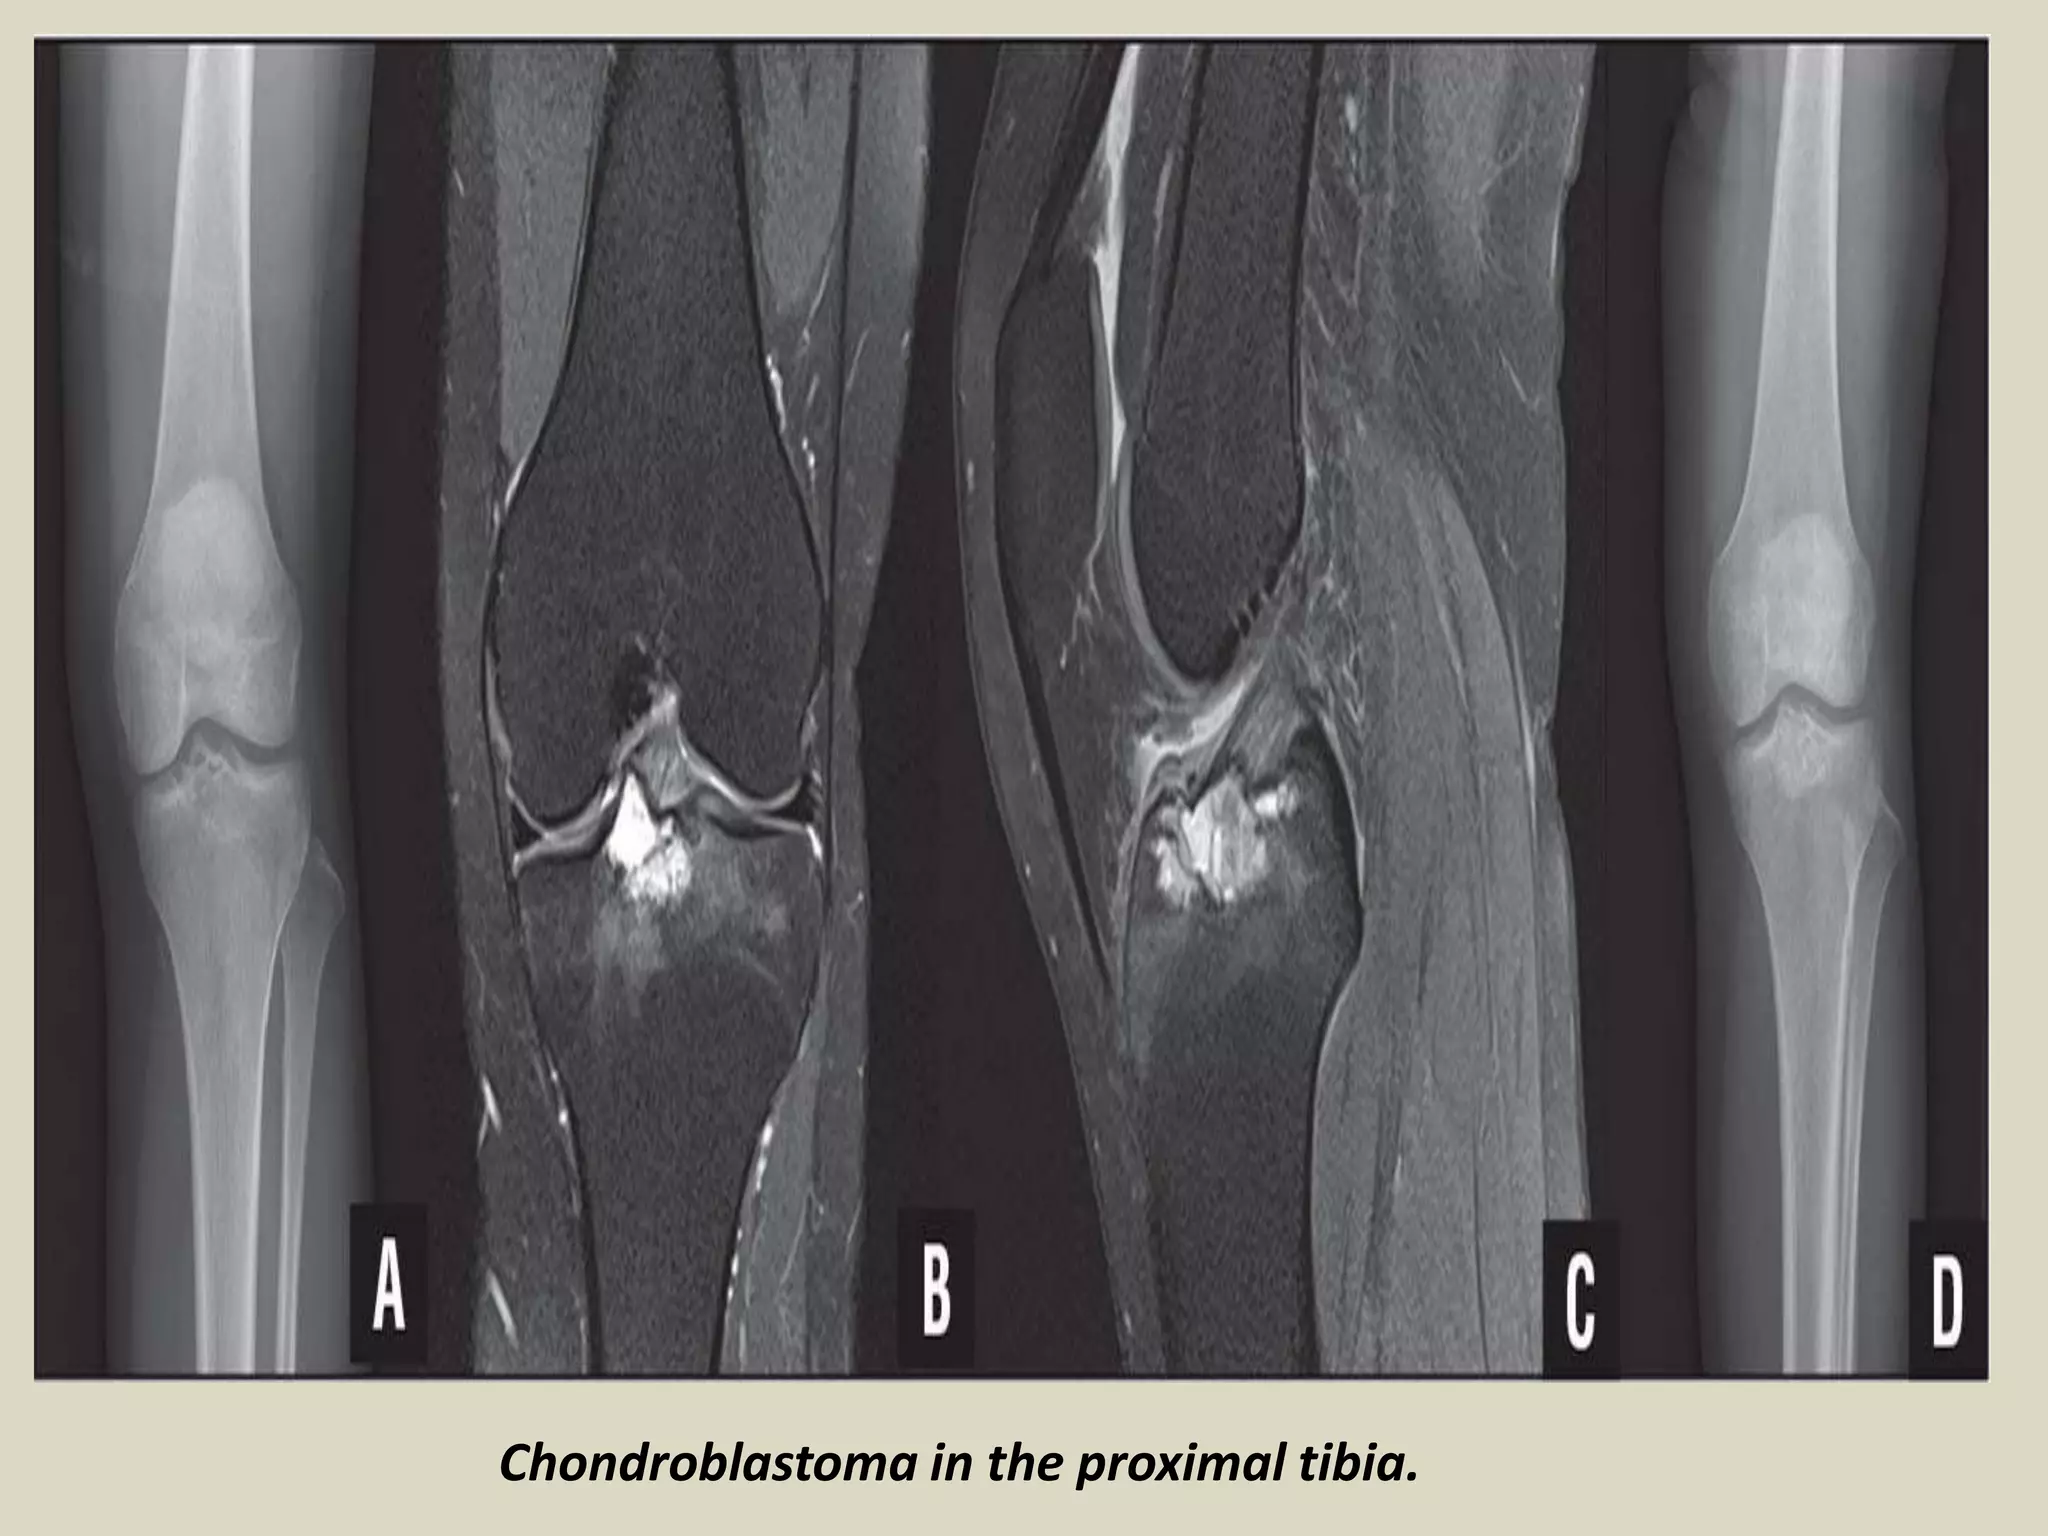

CHONDROBLASTOMA

Definition:

- Benign, cartilage producing neoplasm usually arising in the epiphyses of skeletally immature patients.

Epidemiology:

- Accounts for less than 1% of primary bone tumors.

- Most patients are between 10 and 25 years of age at diagnosis and there is a male predominance.

- Patients with skull and temporal bone involvement tend to present at an older age (40-50 years).

Sites of involvement:

- Usually arises in the epiphyses of the distal and proximal femur, followed by the proximal tibia

and proximal humerus.

- Patients with tumors arising in the flat bones, vertebrae and short tubular bones tend to be

older and skeletally mature, although rare cases have been reported in children.

Clinical findings:

- Majority of patients complain of localized pain, often mild, but sometimes of many years

duration.

- Soft tissue swelling, joint stiffness and limitation, and limp are reported less commonly.

- Minority of patients may develop joint effusion, especially around the knee.

Imaging:

- Typically lytic, centrally or eccentrically placed, relatively small lesions (3 to 6 cm), occupying

less than one half of the epiphysis.

- Shapely demarcated, with or without a thin sclerotic border.

- The presence of sclerotic rim, along with the younger age of the patient, helps to differentiate

chondroblastoma from giant cell tumor of bone, which generally lacks sclerotic border and occurs

in patients less than 20 years.

- Often helpful, matrix calcifications are only visible in about 1/3 of patients.

CHONDROBLASTOMA.

Chondroblastoma in the proximal tibia.